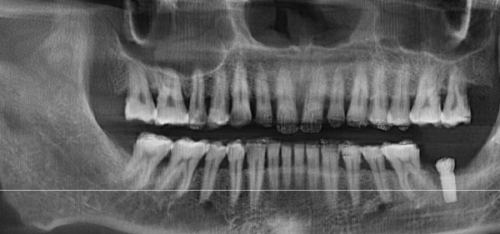

复杂病例(如骨量不足需植骨、上颌窦提升等)会增加费用,可能额外支付2000 - 6000元。因为这些复杂情况需要医生具备更高的技术水平和更丰富的经验,同时也需要使用更多的材料和设备。经验多的医生操作更精细,能够更好地应对各种复杂情况,确保种植牙的长期成效更稳定。

2024年有不同的价格情况。2024年8月28日消息显示,武汉仁爱口腔单颗种植牙价格1840元起一颗,半口种植牙费用1.3万元起,全口种植牙价格3.9万元起,all - on - 6全口种植牙费用在3.9万 - 6万元起。相比于武汉多家口腔机构,武汉仁爱口腔种植牙价格都属于中等偏下的,但是其做种植牙品质并不大折扣。

2024年10月12日的价格信息为,登腾种植牙价格4500元起,美国皓圣种植体价格6500元起,法国安卓健种植系统价格10500元起,瑞士iti种植牙价格12000元起,瑞典诺贝尔种植牙价格12800元起,奥齿泰种植牙价格5600元起,德国种植牙价格8900元起。